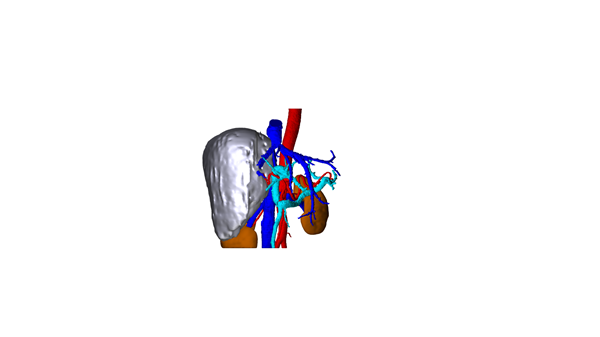

孙女士入院后接受了完整的术前检查及评估,而其结果回报提示肝右叶肿块占位明显,邻近结构受压移位,下腔静脉肝后段受压,管腔明显变窄。黎一鸣教授团队分析认为:肿瘤巨大,若要完整切除肿瘤,需要仔细分离第二、第三肝门,必要时需行下腔静脉人工血管重建。且术中需阻断肝门,手术必须以最快的速度精细的完成,以避免术后患者出现肝功能障碍,手术难度极大。

面对如此高风险的手术,黎一鸣教授、刘清峰副教授、吉鸿副教授、陆宏伟教授等经过认真讨论,组织科室专家反复研究,制定了严密的围术期治疗计划,并与患者家属充分沟通病情及治疗方案。万事俱备,黎一鸣教授团队于2018年4月11日在输血科、麻醉手术科医务人员的大力配合下,在全麻下为该患者实施了肝巨大血管瘤切除术。术中见肿瘤约30*25*20cm大小,已占据整个肝右叶,其病情与术前评估一致。手术历时3小时顺利完成,术中出血量少,术野清晰。黎一鸣教授高超的肝胆外科造诣保证了该项高难度手术的顺利实施。术后患者恢复顺利,拟于近日出院。